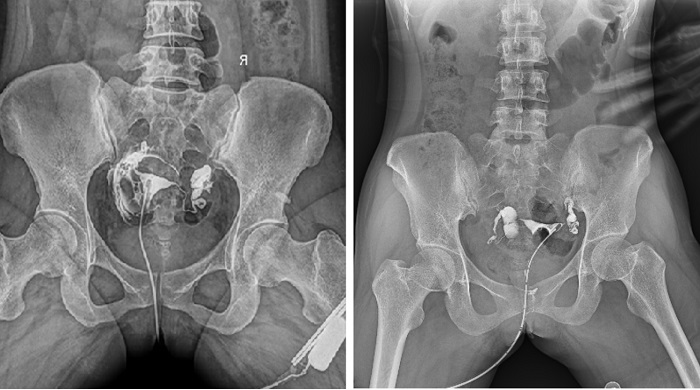

輸卵管性不孕是女性不孕癥的主要原因之一,子宮輸卵管造影檢查損傷小,在有經驗的醫師操作下,能對輸卵管堵塞作出正確診斷,準確率達98%,且具有一定的治療作用。

輸卵管造影檢查可根據造影劑在輸卵管及盆腔內的顯影情況了解輸卵管是否通暢、阻塞部位及宮腔形態,是超聲、CT、核磁、宮腔鏡、腹腔鏡、輸卵管鏡等所無法替代的。作為目前普放領域最先進的影像設備,多功能動態DR進行子宮輸卵管造影檢查,大大超越了過去的檢查技術,更加精準、便捷、高效。

相較于傳統胃腸機,動態DR矩形采集面積大,一次曝光即可顯示整個盆腔,大幅減少觀察時間,可控的瞬時照射避免受檢者吸收過多的X線,對育齡期女性的檢查尤為重要。毫秒級時間內高清點片,可以在造影劑流動的過程中完成拍片,抓拍到關鍵圖像,更加清楚地了解到管腔的具體通暢情況及堵塞部位,對檢查及診斷有非常重要的價值。

此外,應用動態 DR 進行子宮輸卵管造影,還可以在加壓推注下,使部分輸卵管輕、中度堵塞的患者得以通暢,起到一定的治療作用。